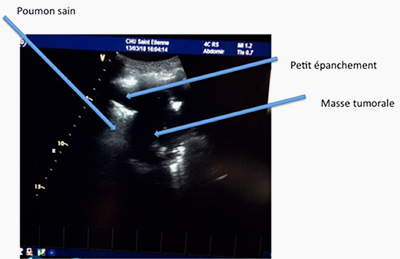

Grâce aux ultrasons, l’exploration de la plèvre se fait sans irradiation ni geste invasif. On peut déceler les pneumothorax (air dans la plèvre), les pleurésies (liquide dans la plèvre) (photo 11) ou repérer une masse ou un nodule pulmonaire au contact de la plèvre (photo 12)